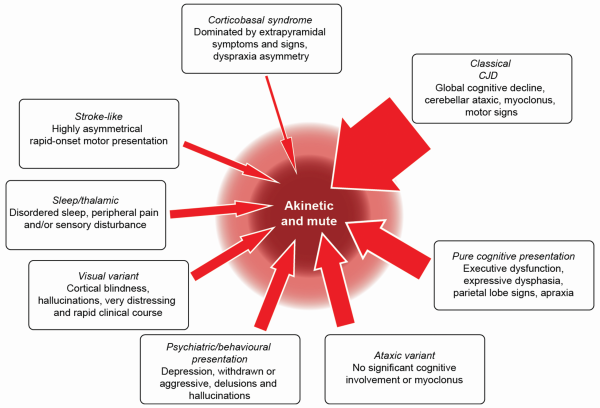

N-methyl-D-aspartate receptor (NMDAR) antibody encephalitis is the most commonly recognised type, initially linked to ovarian teratoma in young women, which remains a prompt to consider the diagnosis. Like in patients with CJD, the history often includes a non-specific prodromal stage, developing into behavioural and psychiatric features, and early generalised and focal seizures that would be very unusual in CJD. Movement disorders commonly develop in CJD, but the specific facial dyskinesia of NMDAR encephalitis would prioritise the disorder. Other flags for the disorder are a CSF pleocytosis, CSF oligoclonal bands, and MR imaging findings (Table 3). These can include T2 or FLAIR hyperintensity of the striatum, thalamus and cortex as might occur in CJD (figure 3) but more typically include abnormalities in other areas, particularly the mesial temporal lobe and hippocampus, and also the brainstem, cerebellum and white matter, often with enhancement or mass effect from inflammation. We recommend testing at least serum in all patients suspected to have CJD and CSF in patients with flags for the disorder.

Figure 3

MR scan of brain in four patients presenting as mimics of prion disease. (A) C9orf72 mutation showing severe generalised atrophy with no parenchymal abnormal signal. Severe atrophy does occur late in some cases of Creutzfeldt-Jakob disease (CJD), but usually diffusion-weighted sequences reveal restricted diffusion. (B) B-cell lymphoma confined at the time of presentation to the brain. Note the extensive white-matter signal change with the normal cortex. Occasionally, the leukoencephalopathic form of CJD has white-matter signal alteration, but this is associated with grey matter destruction. (C) N-methyl-D-aspartate antibody encephalitis with MR imaging showing the pulvinar sign. This sign develops in most cases of variant CJD and has rarely been described with other pathologies. (D) Voltage-gated potassium channel (Casp-1) antibody encephalitis showing unilateral basal ganglia high signal on diffusion-weighted imaging but not on the apparent diffusion coefficient map (scan not shown). Note that the swelling of the caudate is a feature that does not occur in CJD.

Voltage-gated potassium channel (VGKC) complex antibody encephalitis is similarly a crucial mimic of CJD to exclude. Importantly, we now know that pathogenic antibodies are directed at individual members of the VGKC multiprotein complex, for example, LGI1, which may give more specific tests. While associated with a wide range of clinical syndromes, the most commonly confused picture with CJD is one that may include both peripheral manifestations—neuromyotonia, a twitching or stiffness related to spontaneous motor nerve excitability, and autonomic disturbances—and central manifestations, such as brief and frequent seizures affecting ipsilateral face and arm (termed ‘faciobrachial dystonic’), insomnia, memory impairment and behavioural disturbances or more florid manifestations of an encephalitis. Investigation prompts to the diagnosis include hyponatraemia and MR imaging abnormalities of the mesial temporal lobe and hippocampus, which can also involve the basal ganglia (figure 3).

Be concerned about a diagnosis of CJD in the presence of unexplained fever, generalised seizures, hyponatraemia, a facial movement disorder, modest rates of progression (clinical duration >1 year), a CSF pleocytosis, contrast-enhancing MR lesions and white-matter lesions outside the striatum, thalamus and cortex.